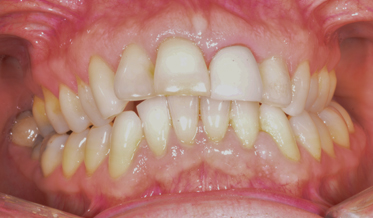

Redefining What Is Possible: Treating Function and Enhancing Esthetics Using a Risk Management System

Kris Swanson, DDS; and Leon Hermanides, CDT